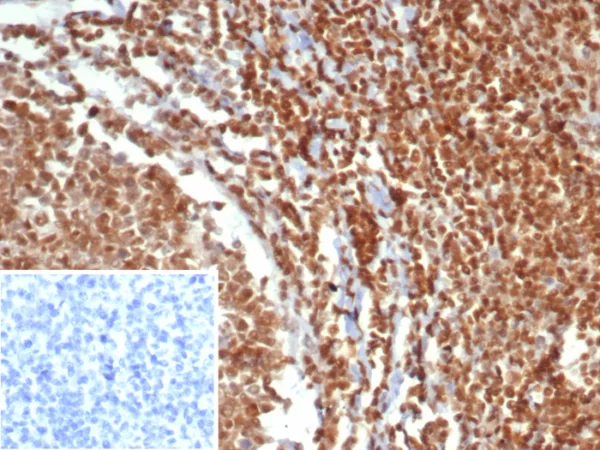

Formalin-fixed, paraffin-embedded human testis stained with MGMT Mouse Monoclonal Antibody (MGMT/7454). Inset: PBS instead of primary antibody; secondary only negative control.